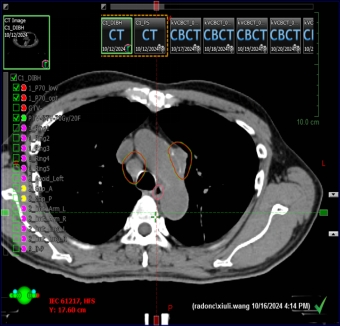

Thu nhỏ kích thước: Hình ảnh chụp cắt lớp vi tính (CT) cho thấy đậm chất thương mại tại buổi tối và các số di căn đã lại đáng kể so với trước khi điều trị.

Kiểm soát di căn: Các vùng bạch huyết trung thất giảm kích thước tối ưu, tìm ra đáp ứng tốt với phác đồ điều trị chiến lược riêng lẻ.